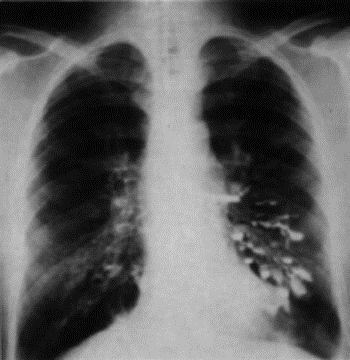

3.4.2 Sarcoidosi (Morbus Boeck, buuk)

Fibrosi polmonare, granulomi duri (malattia generale che pu evolversi in nodi linfatici, derma e anche polmonare: fibrosi polmonare. Si sospetta una forma di tubercolosi.

3.4.2.1 Sintomi

Non specifici, normalmente si scopre per caso in una radiografia polmonare. Si distinguono forme croniche e acute.

3.4.2.2 Prognosi

Il primo stadio e linizio del secondo, possono guarire con cure adatte, il terzo stadio porta a fibrosi con disturbi funzionali polmonari e carico del cuore dx.